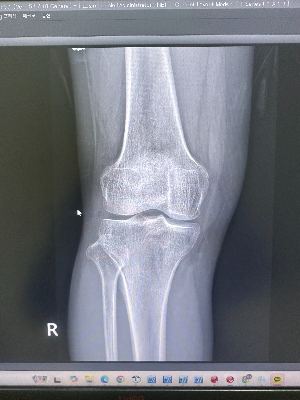

우리의 무릎(슬관절)은 위쪽의 넙다리뼈(대퇴골)와 아래쪽의 정강이뼈(경골)가 만나는 구조로 이루어져 있습니다. 그리고 이 두 뼈가 부딪히지 않고 부드럽게 움직일 수 있도록, 뼈의 끝부분에는 푹신푹신한 스펀지 같은 '관절 연골(물렁뼈)'과 '반월상 연골판'이 완충재 역할을 하고 있죠.

하지만 뼈와 같은 단단한 조직만 하얗게 보여주는 X-ray 검사 특성상, 수분과 단백질로 이루어진 부드러운 연골은 사진에 나타나지 않고 투명한 '빈 공간(검은색)'으로만 보입니다.

방사선사와 판독을 하는 의사 선생님들은 이 '빈 공간'의 간격을 보고 연골의 상태를 유추합니다. 위뼈와 아래뼈 사이의 간격이 넓고 일정하다면 연골이 두껍게 잘 보존되어 있는 것이고, 뼈 사이의 간격이 좁아져 뼈끼리 거의 닿을락 말락 한다면 연골이 닳아 없어졌다는 증거가 됩니다. 이것이 바로 관절염의 기수를 나누는 핵심 기준입니다.

반면, 침대에서 내려와 바닥에 두 발로 꼿꼿하게 서서 찍는 이른바 '체중 부하 촬영(Weight-Bearing View)'은 무릎 관절의 숨겨진 진짜 민낯을 적나라하게 보여줍니다.

환자분이 두 발로 바닥을 딛고 서는 순간, 환자분의 체중(몸무게)과 지구의 중력이 무릎 관절을 위에서 아래로 강하게 짓누르기 시작합니다. 이때 연골이 건강하고 두껍게 남아있는 정상적인 무릎이라면, 체중이 실리더라도 연골이 스프링처럼 버텨주기 때문에 뼈와 뼈 사이의 간격이 일정하게 유지됩니다.

하지만 퇴행성 변화로 인해 연골이 닳아 얇아지거나 찢어진 관절염 환자라면? 쿠션 역할을 해줄 연골이 없기 때문에, 체중이 실리는 순간 위쪽 넙다리뼈가 아래쪽 정강이뼈로 푹 주저앉아 버리게 됩니다. 서서 찍은 X-ray 사진을 보면, 뼈와 뼈가 쾅 부딪혀 공간이 아예 사라져버린(관절 간격 협소) 참담한 모습을 1초 만에 확인할 수 있습니다. 특히 한국인은 좌식 생활의 영향으로 무릎의 안쪽 연골이 주로 닳는 'O자형 다리(내반슬)' 변형이 흔한데, 서서 양쪽 무릎을 동시에 찍어보면 다리가 얼마나 휘었는지 그 각도까지 완벽하게 계산해 낼 수 있습니다.

아까 저에게 툴툴거리며 간신히 서서 사진을 찍으셨던 우리 할머니, 진료실에 들어가시고 나서 상황이 180도 바뀌었습니다. 누워서 찍었을 때는 뼈 사이가 벌어져 있어서 "어? 연골이 아직 남으셨나?" 싶었는데, 막상 서서 찍은 사진을 모니터에 띄우니 체중에 짓눌려 윗뼈와 아랫뼈가 완전히 딱 달라붙어 있는 '말기 관절염'의 민낯이 그대로 드러났거든요.